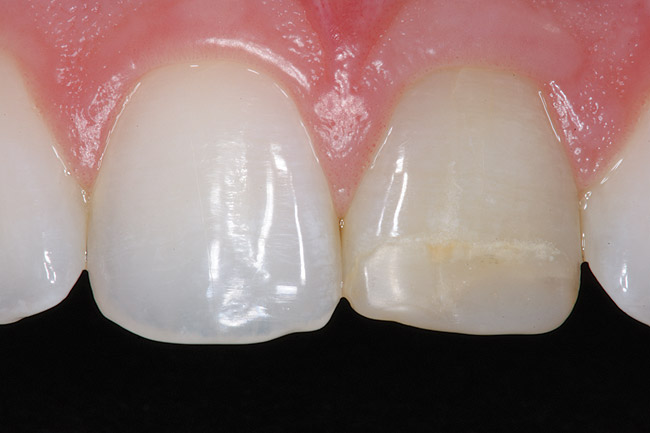

Replacement of existing restorations is responsible for 75% of all operative dentistry.15,19 The reasons for placement and replacement of restorations of direct restorative materials include: primary caries (Figure 1 and Figure 2); recurrent caries (Figure 3); poor margins (Figure 4 and Figure 5); restoration fracture (Figure 6 and Figure 7); tooth fracture (Figure 8); esthetics (Figure 9); non-carious tooth structure lost (attrition, abrasion, abfraction, erosion) (Figure 10); and pain/sensitivity.

Fig. 9 Discolored, unesthetic Class IV composite resin on the maxillary left central incisor.

Figure 9: Discolored, unesthetic Class IV composite resin on the maxillary left central incisor.

Figure 9